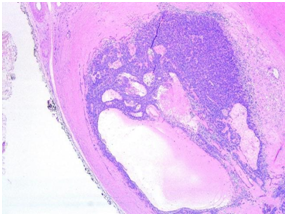

Diagnosis was a complete margin excision Eccrine Spiradenoma with an unusual cystic pattern (Figures 5)(Figure 6) having a luminal cell population, CK8/18 positive (Figure 7), and a basal and myoepithelial cells population, p63 positive (Figure 8).

Figure 5 Eccrine Spiradenoma with an unusual cystic pattern. (H&E stain, ob. x2.5).